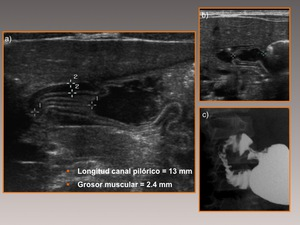

Caracterizada por un engrosamiento anormal del músculo pilórico, lo que lleva a una obstrucción de la salida gástrica. Esta condición es una causa común de vómitos no biliosos en lactantes y generalmente se presenta entre las 2 y 12 semanas de vida.

El diagnóstico se realiza principalmente mediante ecografía, que muestra un alargamiento constante y un engrosamiento de la pared del píloro, con una longitud del canal pilórico superior a 18 mm y un grosor muscular de al menos 4 mm.

Ejemplos de estenosis pilorica hipertrofica infantil.